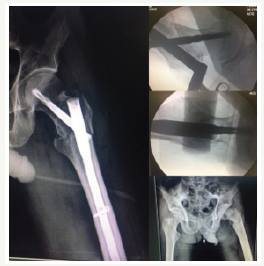

Total number of patients were 83. about 49 women and 34 man. After one year we assessed mortality rate As we got, 24% (20 patients) mortality rate after one year and 6% (3 man and 2 women) death in first month. Of this number (20 patients) 12 were women (14.4%) and 8 were man (9.6%) (Figure 1-4).

Figure 4:OTA/31A3.

After searching data base like Medline there is few studies which assesses a relationship between mortality and stable device have been found, conversely, we thought it maybe exist so design this study stablished. We include all unstable extra-capsular acute hip fracture in patients above 60 years old who brought to our hospital for one year and underwent surgery with helical blade short femoral nails. Before surgery all patient sent for cardiac test and any other test if he/she suffered before admission, all optimization was done in 3-5 days. Reduction was done by traction table closely and nailing was done per cutaneous by one design. All the surgeries done by one well experienced Orthopeadic surgeon.